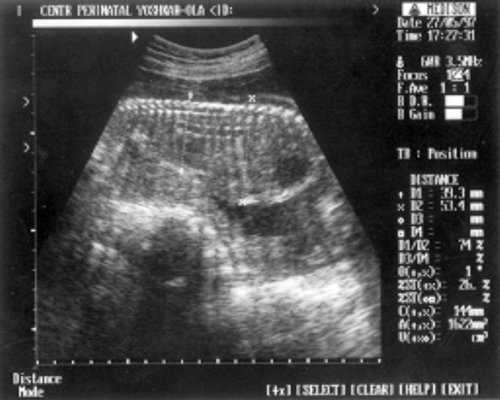

ДБ (длина бедра) = 24 мм - 17 нед. (рис. 2)

- ДБ (длина бедра) = 24 мм - 17 нед. (рис. 2)

Рис. 2. УЗИ плода - бедро.